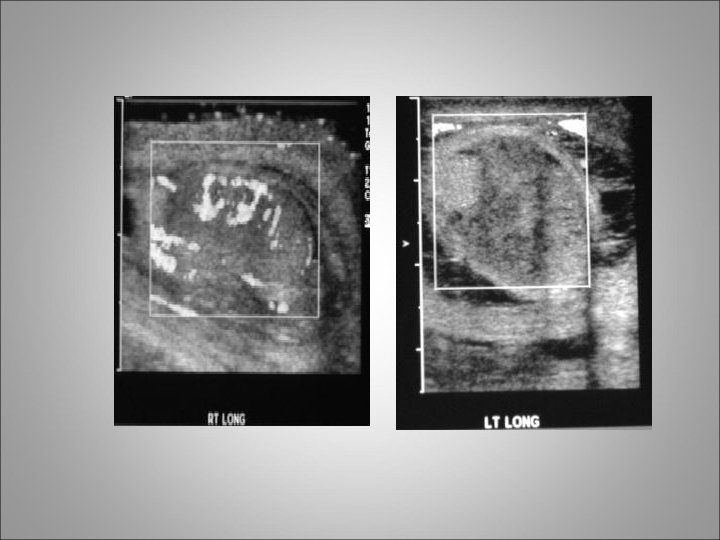

Testicular Trauma • Testicular rupture or fractured testis refers to a rip or tear in the tunica albuginea resulting in extrusion of the testicular contents • Blunt trauma accounts for approximately 85% of cases, and penetrating trauma accounts for 15% • As many as 80% of hematoceles (blood in the tunica vaginalis) are associated with testicular rupture

Clinical diagnosis • Patients typically present to ER with a straightforward history of injury • Symptoms include extreme scrotal pain, frequently associated with nausea and vomiting • Physical examination often reveals a swollen, severely tender testicle with a visible hematoma • Scrotal or perineal ecchymosis may be present • When evaluating a patient with a clinical history of only minor trauma, do not overlook the possibility of testicular torsion or epididymitis

Clinical diagnosis • For penetrating injuries, determine the entrance and exit sites of the wound. • Screening urinalysis is important to rule out urinary tract infection or epididymo-orchitis • Scrotal ultrasound imaging with Doppler studies is valuable for diagnosing and staging testicular injuries • The presence of a disrupted tunica albuginea is pathognomonic for testicular rupture

Indications for scrotal exploration • Uncertainty in diagnosis after appropriate clinical and radiographic evaluations • Disruption of the tunica albuginea • Large hematocele • Absence of blood flow on scrotal ultrasound images with Doppler studies

scrotal exploration • Clinical hematoceles that are expanding or of considerable size (eg, 5 cm or larger) should be explored • Collections of smaller size are also often explored, because it has been shown that such practice allows for more optimal pain control and shorter hospital stays • If the testis is fractured, testicular debridement and surgical closure of the tunica albuginea are necessary